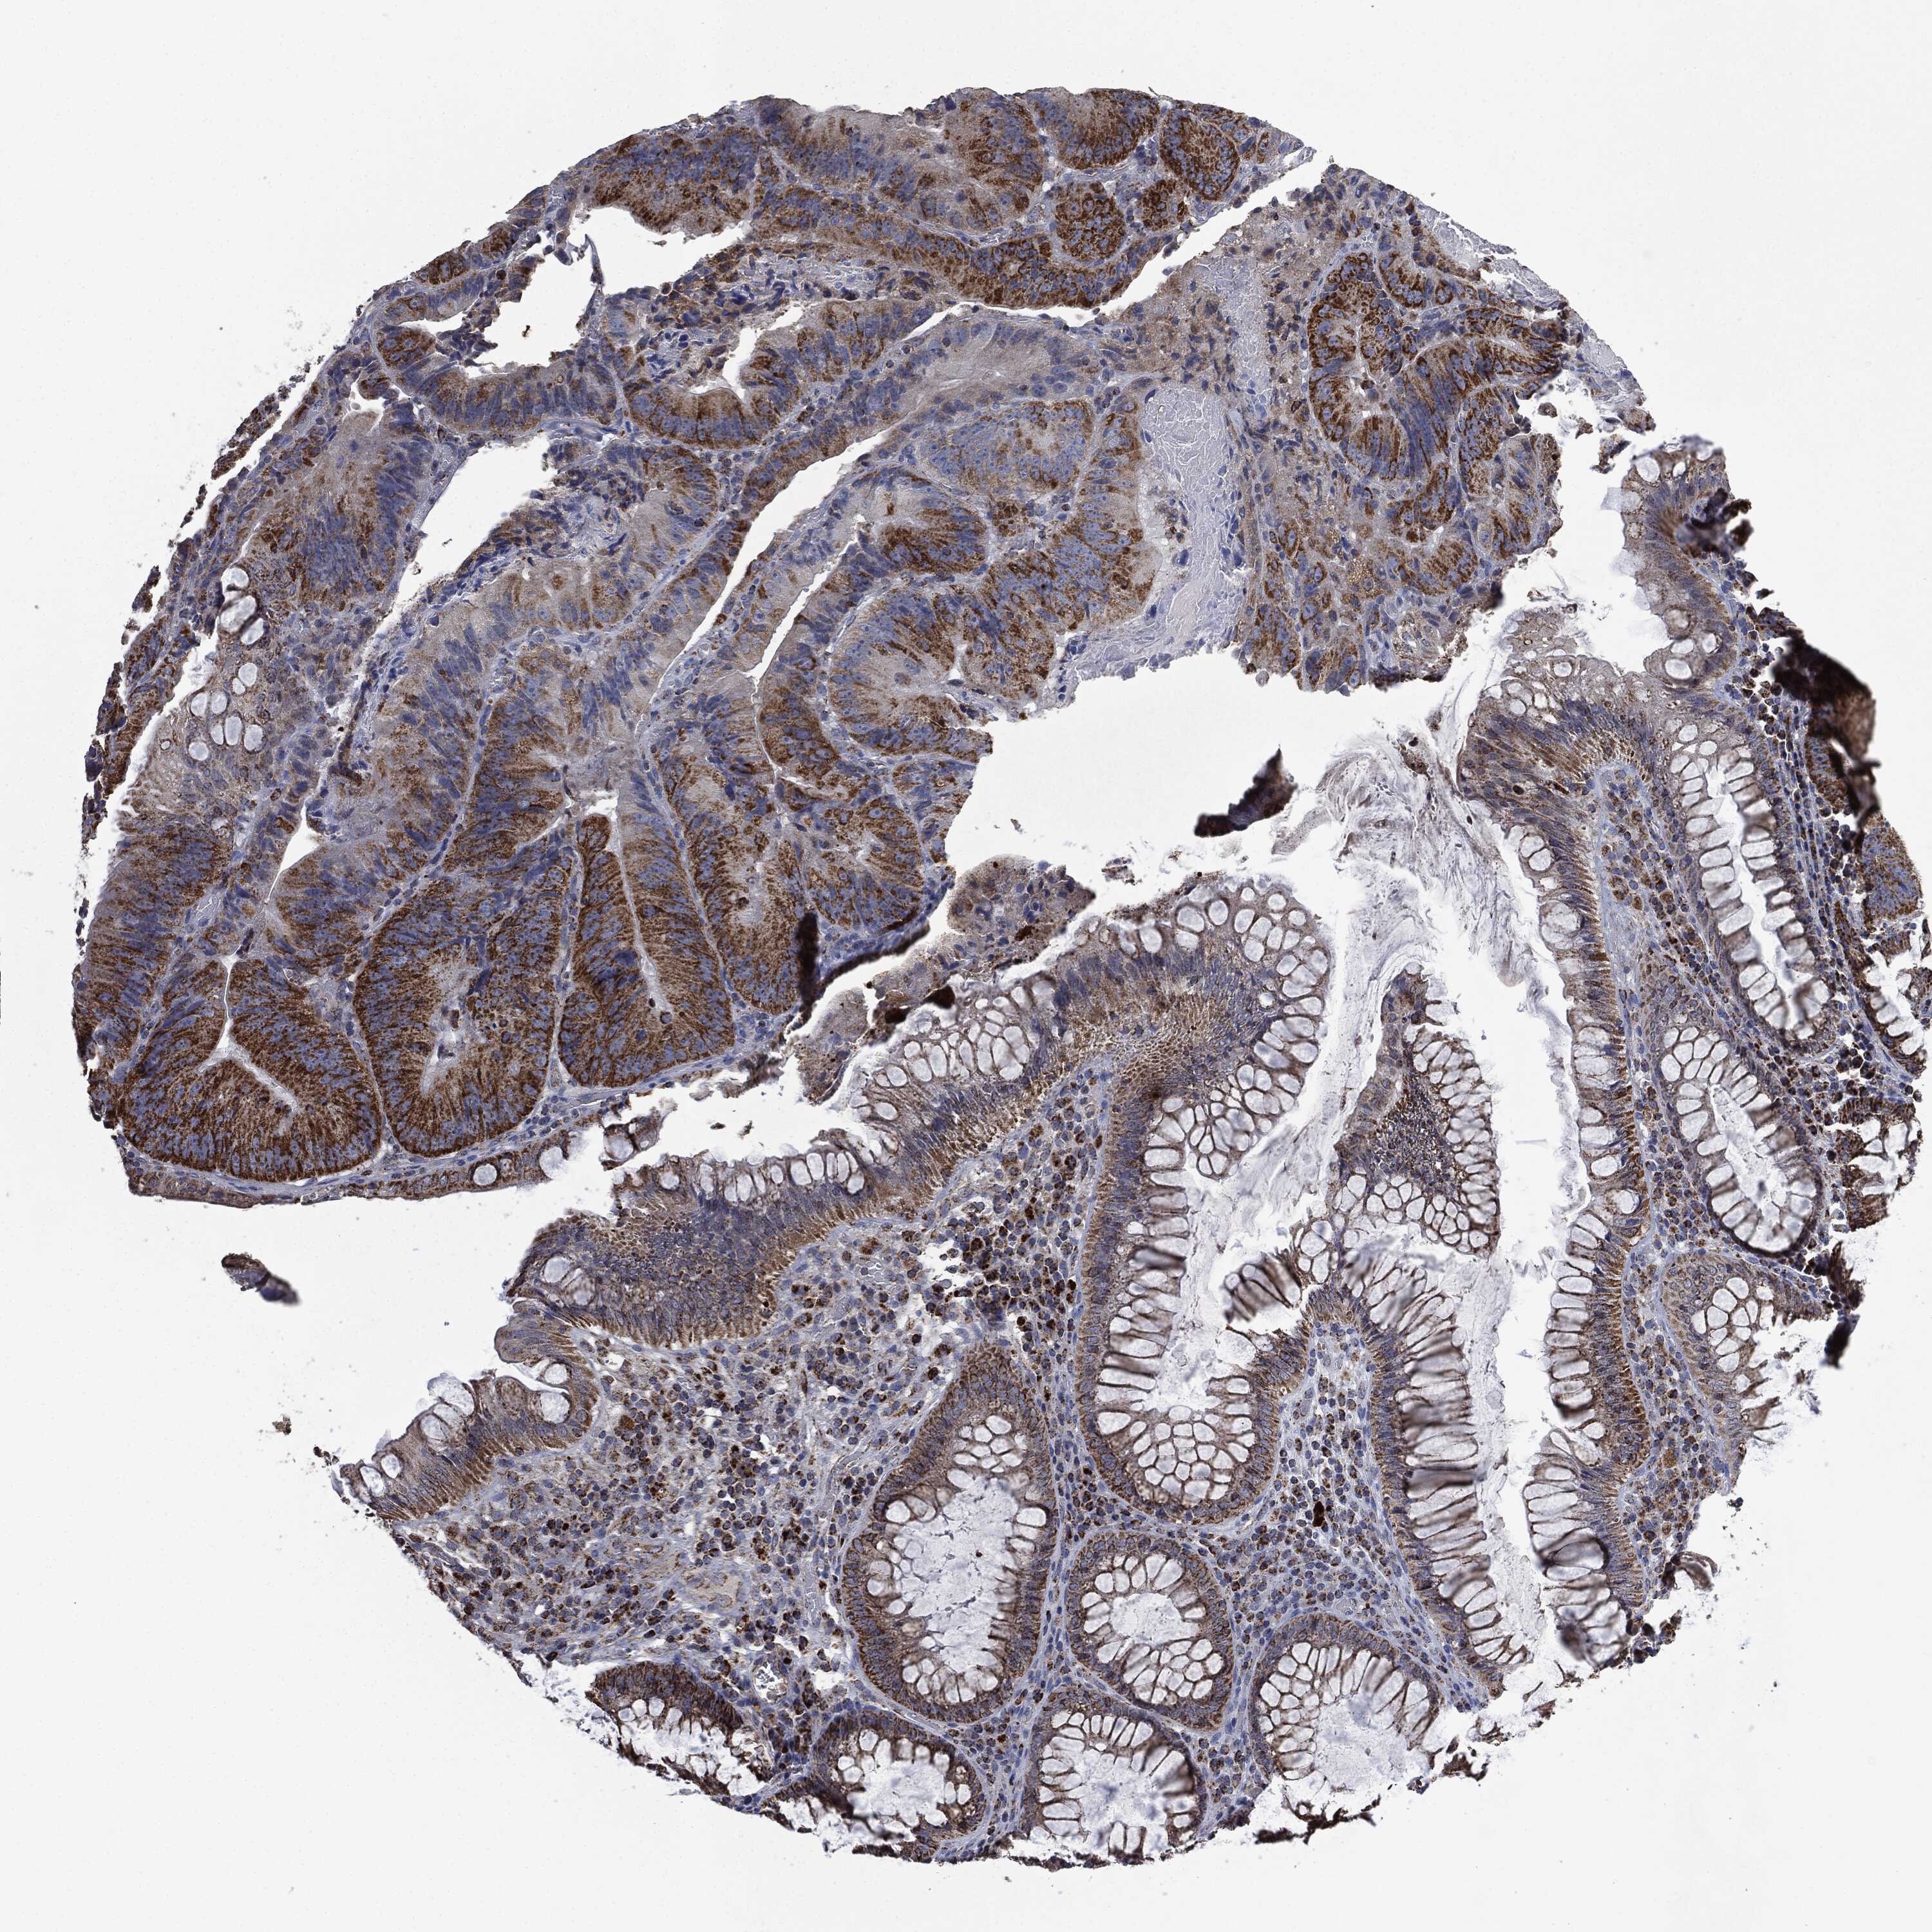

CANCER COLORECTAL CANCER Show tissue menu

Colorectal cancer

Human cancer